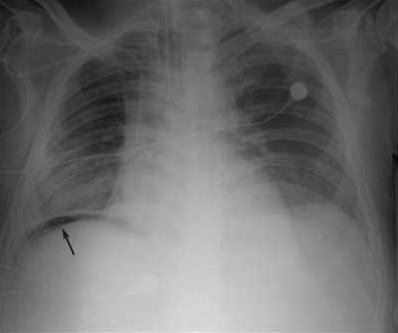

<div id="article-content-body"><p>My patient is an 82-year-old woman with a history of coronary artery bypass grafting (CABG), chronic obstructive pulmonary disease (COPD), pulmonary...